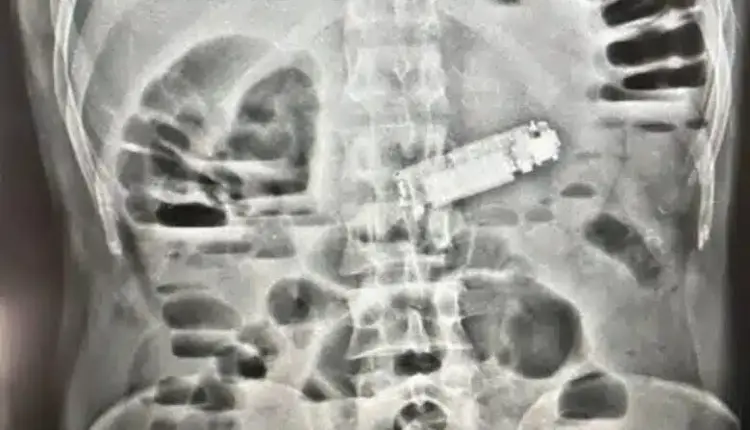

الفحوصات تكشف عن الهاتف داخل معدة المريض

أجرى الفريق الطبي للمريض كافة الفحوصات اللازمة والأشعة التشخيصية، التي أظهرت وجود جسم غريب يعيق عمل المعدة، ليتبين أنه هاتف محمول تسبب في انسداد فتحة البواب، وهو ما كان وراء الأعراض الخطيرة التي يعاني منها المريض